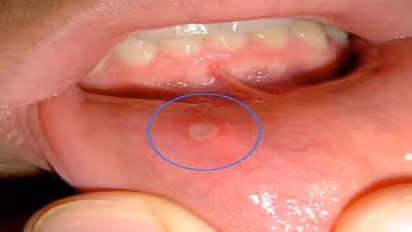

வாயின் கொப்புளங்கள் உண்டாகி அவதிப்பட்டீங்களா? அப்படி உண்டாவதைத்தான் ‘வாய்ப்புண்’ (MOUTH ULCER) என நாம் அழைக்கிறோம். இதனை போக்க சில எளிய வழிகள்.